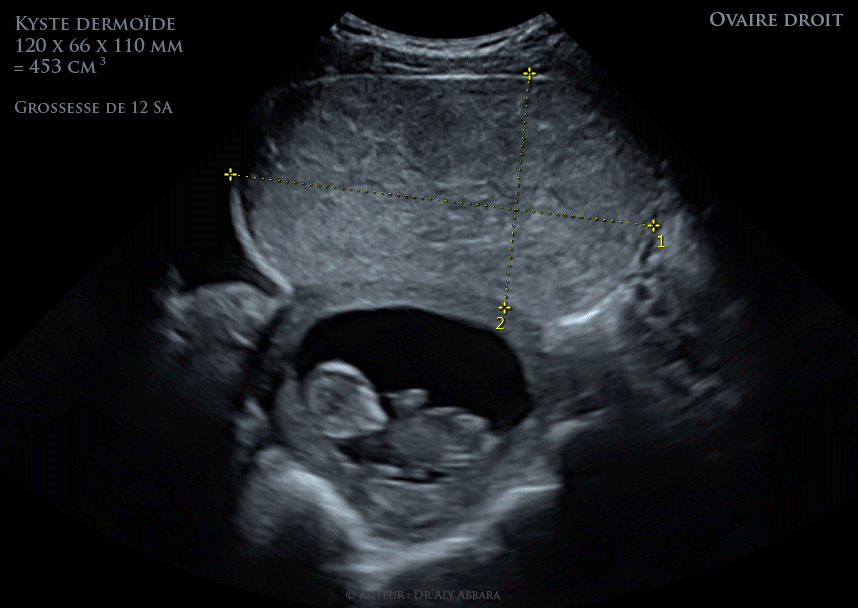

Ovaire Droit Volumineux Teratome Benin Kyste Dermoide Chez Une Femme Enceinte De 12 Sa Echographie Et Images Cliniques